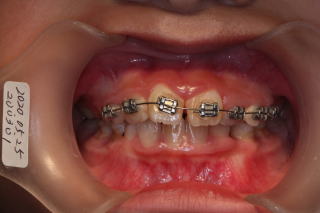

2020年03月02日 初診

上顎前歯叢生反対咬合

2020年03月16日

反対咬合を改善するため咬合挙上

ブラケットセット、萌出のスペースを確保するために、

オープンコイルセット